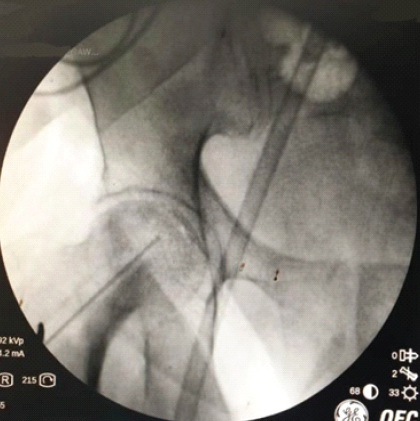

We present a case in which a metal interference screw became sunken within the femoral neck during bilateral hip core decompression and AALCO injection, as shown in Fig. 1.

Figure 1: Interference screw sunken in the femoral neck.